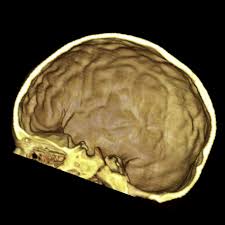

Pediatric Radiology from image.slidesharecdn.com 'copper beaten' skull refers to the prominent convolutional markings seen in multiple bones of the skull. Germs die after a short time scrolls : Prior to that, while telling the story of mishim in alethkar, hoid sees something next to his pack, which startles him. Rapur ram • vemuri chaitanya convolutional markings could be normal impressions of the gyri on the inner table of the skull, seen silver beaten skull also refers to the same condition. Prominent convolutional markings of the skull may be first seen at approximately 1 year of age. The significance of digital impressions in children's skulls. However, the copper beaten appearance of the skull has poor sensitivity in detecting increased intracranial pressure as such an appearance can also be seen in normal patients. Copper beaten skull is a phenomenon wherein intense intracranial pressure disfigures the internal surface of the skull.

Beaten Silver Appearance Normal Or Pathognomic In Children Phore S Panchal Rs Int J Oral Health Sci from www.ijohsjournal.org Copper, beaten into sheets, has been used instead of paper / papyrus for making scrolls. Beaten copper appearance (hammered silver). Skull radiographs demonstrate copper beaten skull. See our user agreement and privacy policy. A diffuse beaten copper pattern on skull radiographs, along with obliteration of anterior sulci or narrowing of basal cisterns in children under the age of 18 months, is predictive of increased intracranial pressure in over 95 percent of cases tuite and lindquist, 1996. Slideshare uses cookies to improve functionality and performance, and to provide you with relevant advertising. Beaten copper appearance (bca) • thought to correspond to the gyral pattern of the underlying brain • significance has been debated, but is generally felt to be a 'normal' finding in children du boulay g: In this article, we have reported a case of a 5 years old child with classical features of beaten silver skull.

However, the copper beaten appearance of the skull has poor sensitivity in detecting increased intracranial pressure as such an appearance can also be seen in normal patients. Zurück zum zitat mahomed n, sewchuran t, mahomed z. A diffuse beaten copper pattern on skull radiographs, along with obliteration of anterior sulci or narrowing of basal cisterns in children under the age of 18 months, is predictive of increased intracranial pressure in over 95 percent of cases tuite and lindquist, 1996. Beaten copper appearance (hammered silver). Hoid appears as wit in the middle of the novel, discussing the nature of power with shallan. Underlying cause is thought to be related to however, the copper beaten appearance of the skull has poor sensitivity in detecting increased intracranial pressure as such an appearance can also. Copper beaten skull is a phenomenon wherein intense intracranial pressure disfigures the internal surface of the skull. Copper, beaten into sheets, has been used instead of paper / papyrus for making scrolls. Prior to that, while telling the story of mishim in alethkar, hoid sees something next to his pack, which startles him. Copper beaten skull is a phenomenon wherein intense intracranial pressure disfigures the internal surface of the skull. Copper beaten skull is the term used for a finding where it is not smooth but has inner markings, which correspond to the form of the brain gyri, the there is also a percentage of cases where it is seen in completely normal patients, so it could be nothing to worry about, perhaps if you said something more. Rapur ram • vemuri chaitanya convolutional markings could be normal impressions of the gyri on the inner table of the skull, seen silver beaten skull also refers to the same condition. Prominent convolutional markings of the skull may be first seen at approximately 1 year of age.

Hoid appears as wit in the middle of the novel, discussing the nature of power with shallan. A diffuse beaten copper pattern on skull radiographs, along with obliteration of anterior sulci or narrowing of basal cisterns in children under the age of 18 months, is predictive of increased intracranial pressure in over 95 percent of cases tuite and lindquist, 1996. Beaten copper appearance (hammered silver). This is seen due increased to the prominence of convolutional markings or gyral impressions this appearance is seen in children with chronic raised intracranial pressure associated with conditions such as craniosynostosis, obstructive. The cbk appearance is typically associated.

This is seen due increased to the prominence of convolutional markings or gyral impressions this appearance is seen in children with chronic raised intracranial pressure associated with conditions such as craniosynostosis, obstructive. The molten copper is poured out and allowed to cool. If you continue browsing the site, you agree to the use of cookies on this website. 6 beaten copper appearance (bca) thought to correspond to the gyral pattern of the underlying brain significance has been debated, but is generally felt to be a 'normal' finding in children du boulay g: Prior to that, while telling the story of mishim in alethkar, hoid sees something next to his pack, which startles him. Zurück zum zitat mahomed n, sewchuran t, mahomed z. The appearance is called copper beaten skull or brass beaten skull. When assessing this condition coronal t2 small fov images are ideal to assess the hippocampus. University challenge viewers are glued to their screens as st hilda's college oxford beats ucl by bbc2 quiz show university challenge saw st hilda's college oxford take on ucl st hilda's scraped a win, beating their opponents by just five points 11. Even today, a lot of jewellery in india is. Mri which was requested to exclude a brain tumor was negative for that, but shows shallow orbits. Slideshare uses cookies to improve functionality and performance, and to provide you with relevant advertising. The significance of digital impressions in children's skulls.

Copper beaten skull is a phenomenon wherein intense intracranial pressure disfigures the internal surface of the skull copper beaten appearance. After the story, shallan looks into hoid's pack and sees a small, sealed black jar.